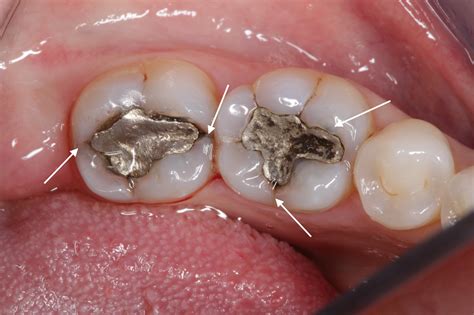

• Large Fillings: Teeth with very large fillings have less natural structure remaining, making them more susceptible to fracturing under pressure.

• Dental Crowns: This is a very common solution for a crack in tooth. A crown (a cap) covers the entire tooth, providing support and preventing the crack from spreading further under the force of chewing.